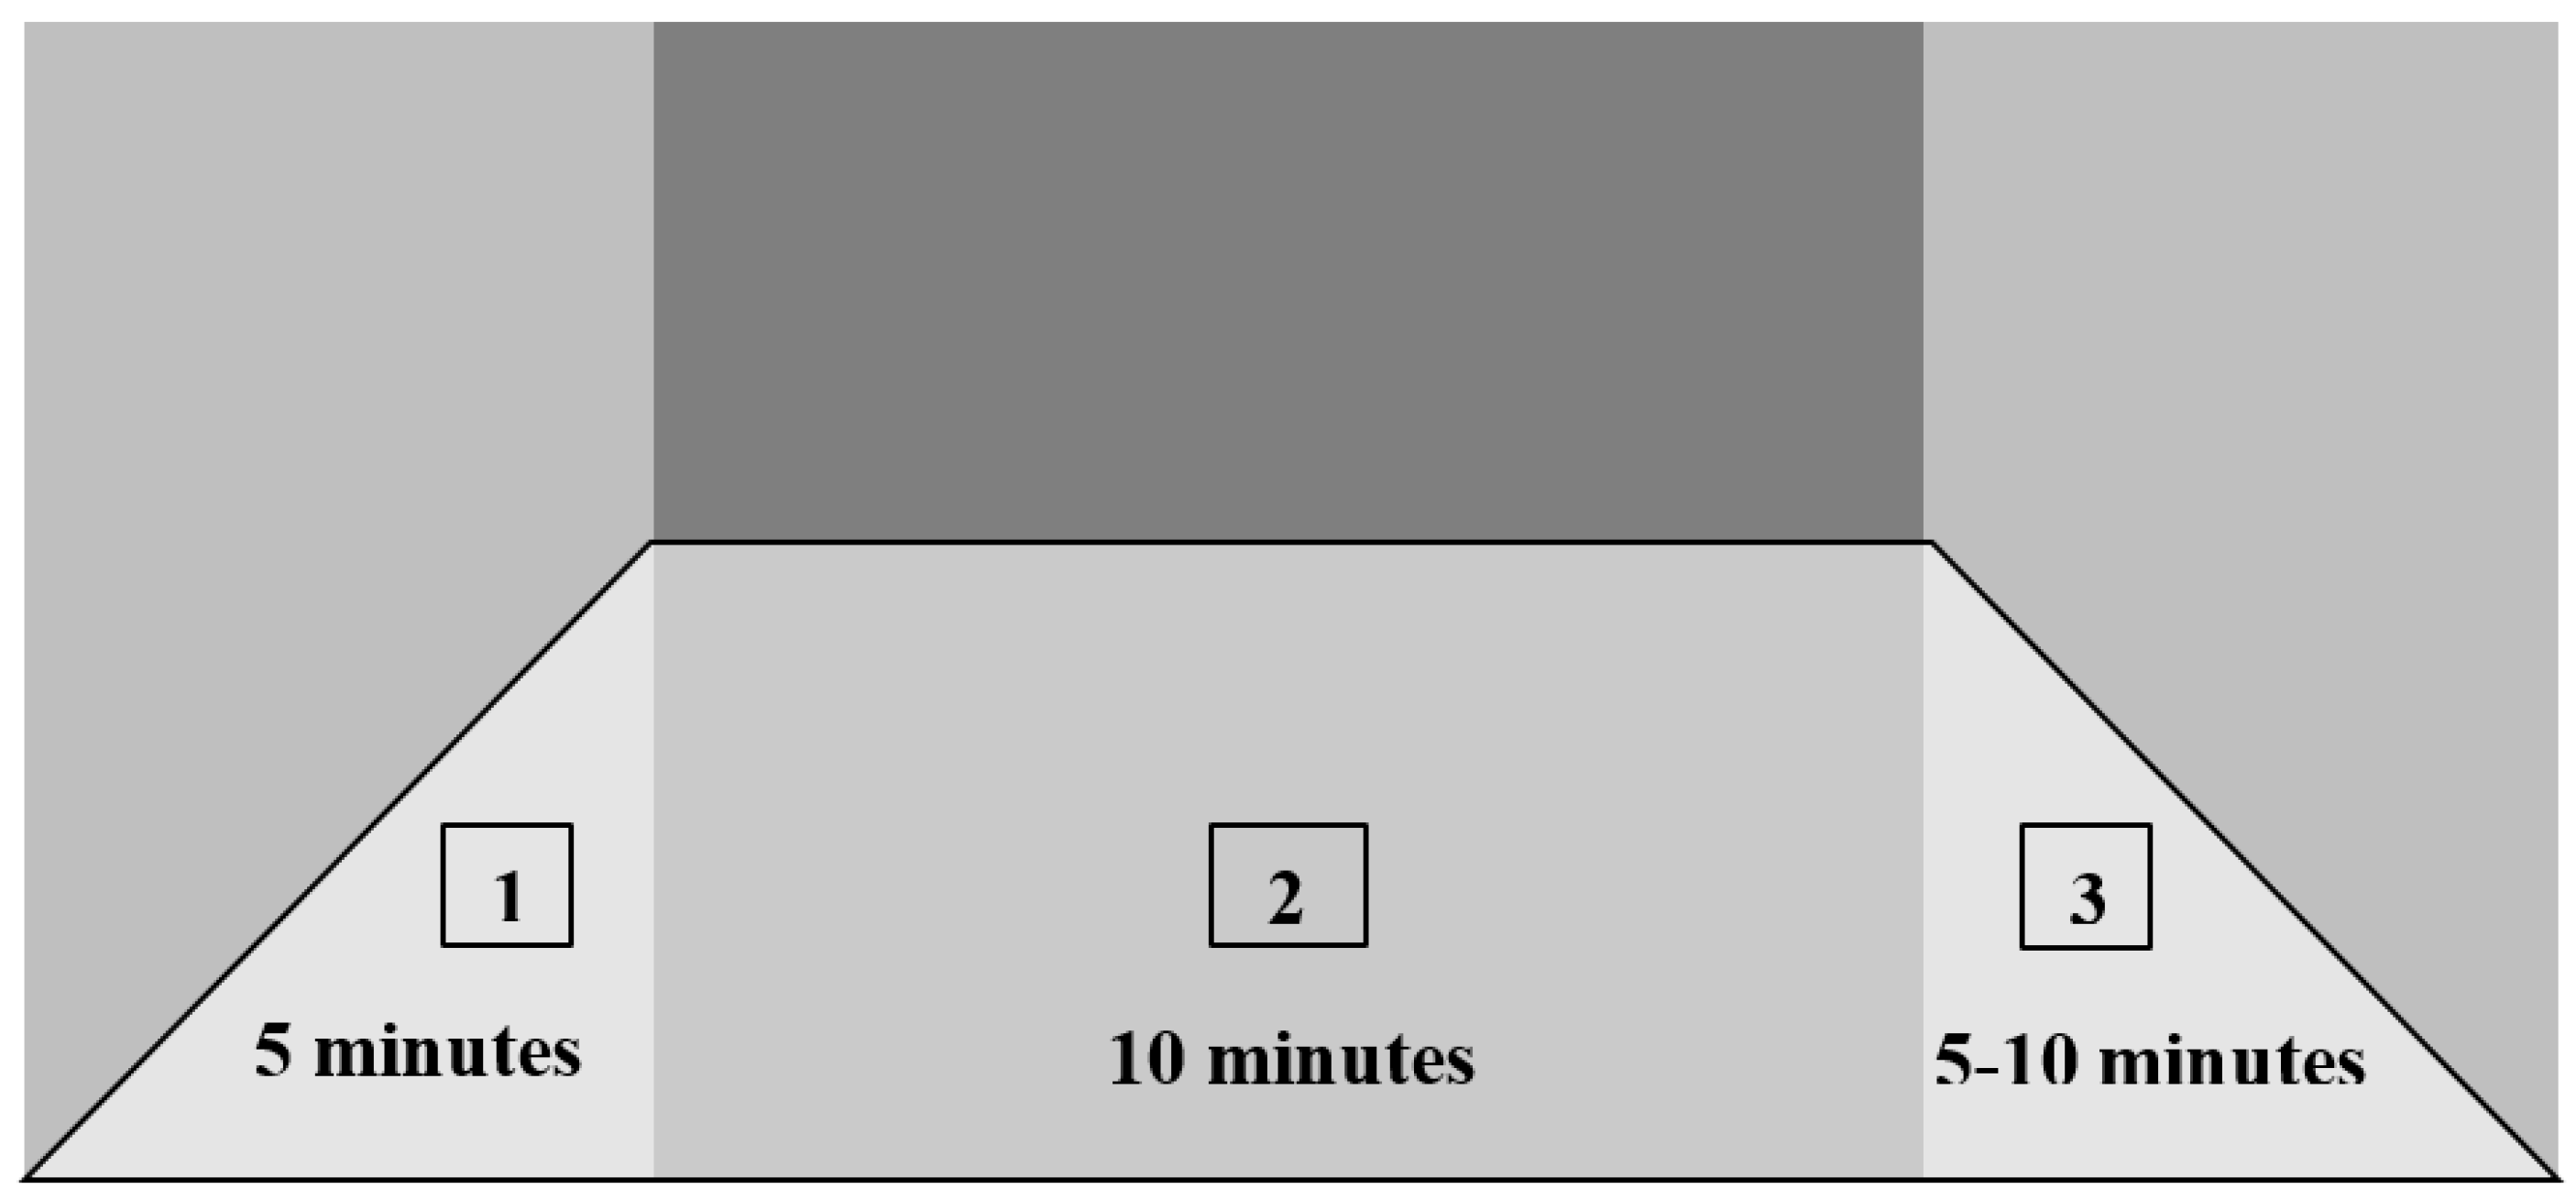

2. Detailed Case Description